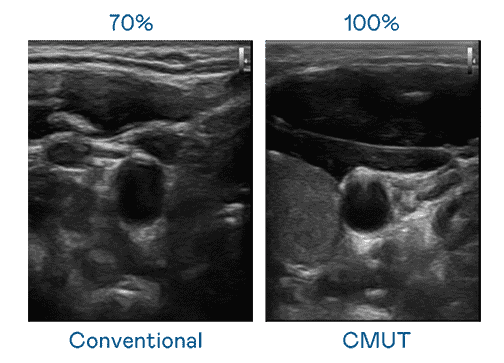

CMUT 技术是一种用电容式微机电元件来产生超音波讯号的技术。。。。与传统 PZT 压电式技术相比,,CMUT 频宽增加 30%,,,,更宽频的超音波讯号让影像解析度大幅提升,,,,是实现高影像品质医疗超音波扫描、、促进精准医疗发展的关键技术。。。。

大频宽带来超清晰影像

超音波影像的解析度高低,,,,首先取决于探头能发出的讯号频宽。。。z6mg·人生就是博 CMUT 可提供高清晰的超音波讯号,,,,提供高频宽、、高灵敏度、、、、影像纹理细节更高的超音波影像,,协助医护人员缩短影像判读时间及利用精准的医疗影像进行诊断。。。